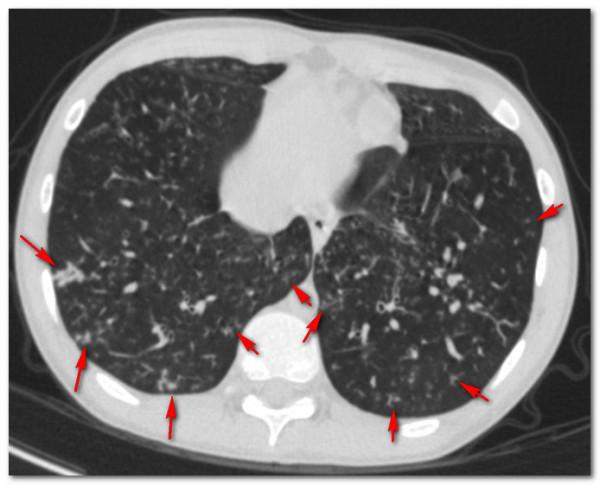

好在小夥肺功能雖然有阻塞,總體上沒有影響到生活,說話中氣很足,就是痰多,而且很難排出來,做了個胸部CT肺上面除了支氣管擴張之外,長了很多結節,就像一把“芝麻”撒在了肺上,有些芝麻恰巧撒在了擴張的終末細支氣管的旁邊,就像樹枝上發出的芽,所以稱為“樹芽徵”。

其實他這一次的病情比以前還好一點,以前的芝麻還要多,這一次住院主要是覺得肺裡面的痰太多了,咳不乾淨,老是聽到自己肺裡有呼嚕呼嚕的聲音,所以過來做氣管鏡吸痰,於是給他安排了氣管鏡。

很多看過我科普的朋友應該知道是什麼疾病了,集齊了鼻竇炎、大量痰、呼吸阻塞、支氣管擴張、樹芽徵等這幾個要素的肺病,診斷就已經很明確了,那就是瀰漫性泛細支氣管炎,這個病首先由日本學者報道,需要長期使用大環內酯類藥物(比如紅黴素、阿奇黴素)治療,這個病如果不認識他,很有可能被長期誤診為慢性支氣管炎或者慢性阻塞性肺病,如果認識了他就好診斷了,早期診斷沒有形成支氣管擴張的話,口服阿奇黴素效果很好,甚至能治癒。